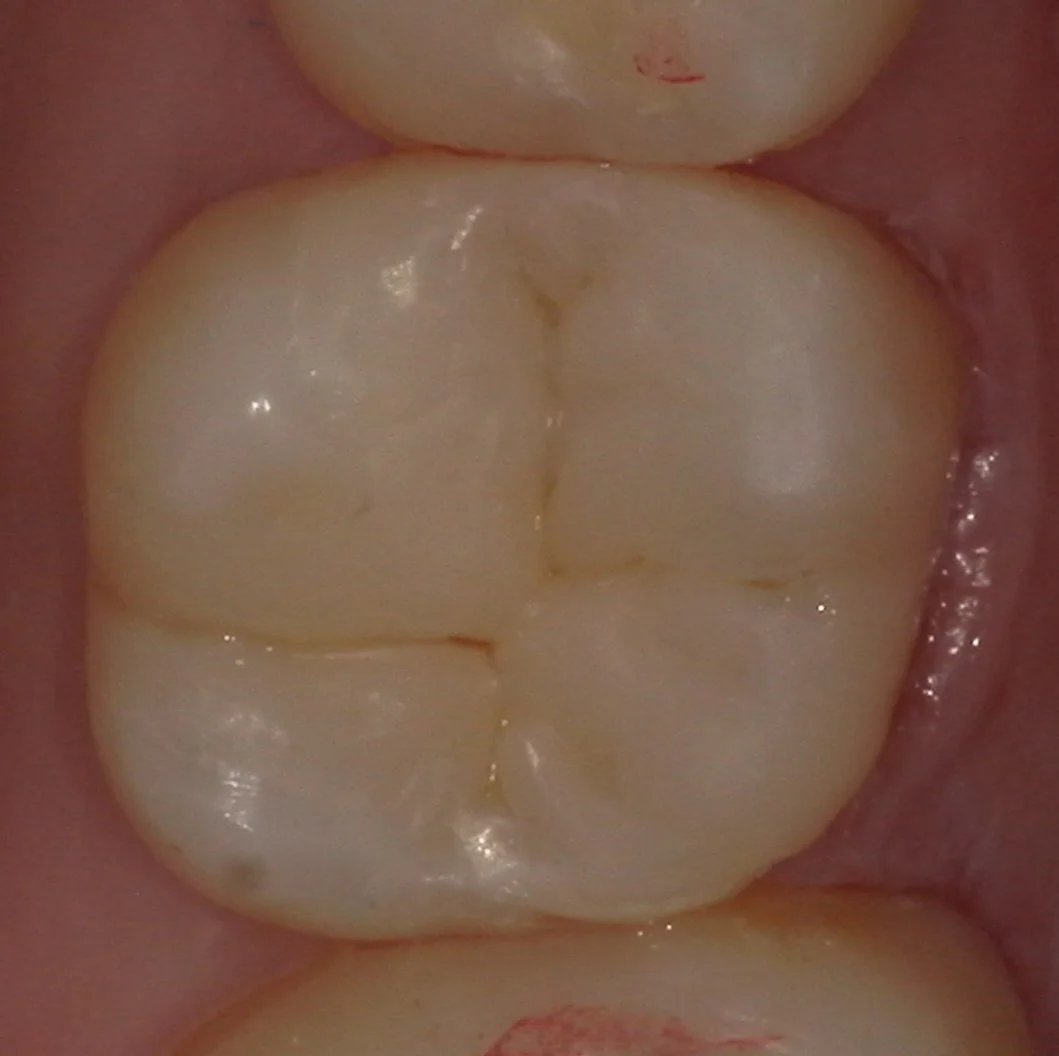

では術前の写真からです。

今回は2方向からの写真を撮影させていただいたので、2つの角度を載せていきますね。

まずは術前の噛む面からの写真です。

歯の側面も同時に治療したケース。|坂寄歯科医院(取手市藤代)